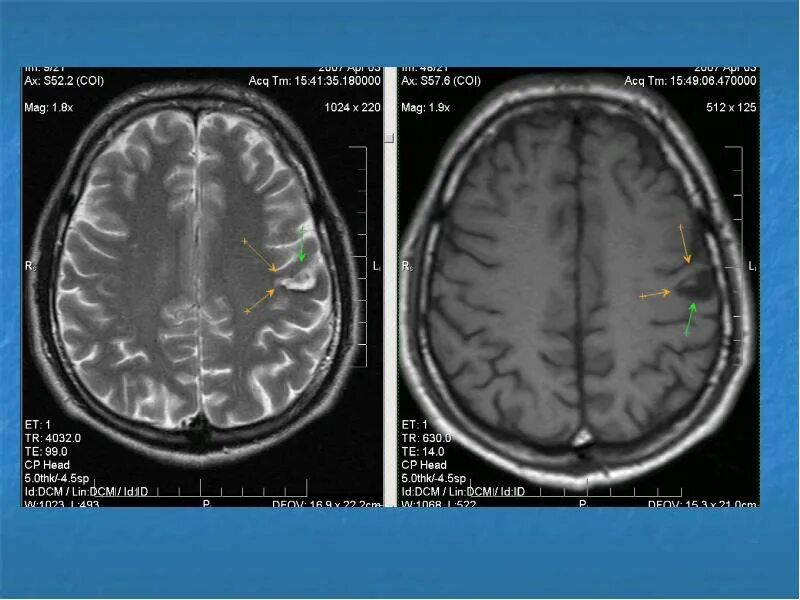

Очаговые диффузные изменения головного мозга